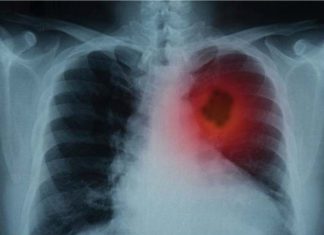

Kjo mënyrë do u pastrojë mushkëritë duhanpirësve

Mushkëritë luajnë rol të rëndësishëm në trupin tonë pasi që janë përgjegjëse për furnizimin me oksigjen dhe largimin e dyoksidit të karbonit.

Dhe, duke marrë parasysh që ato janë vazhdimisht duke punuar, është detyrë e...